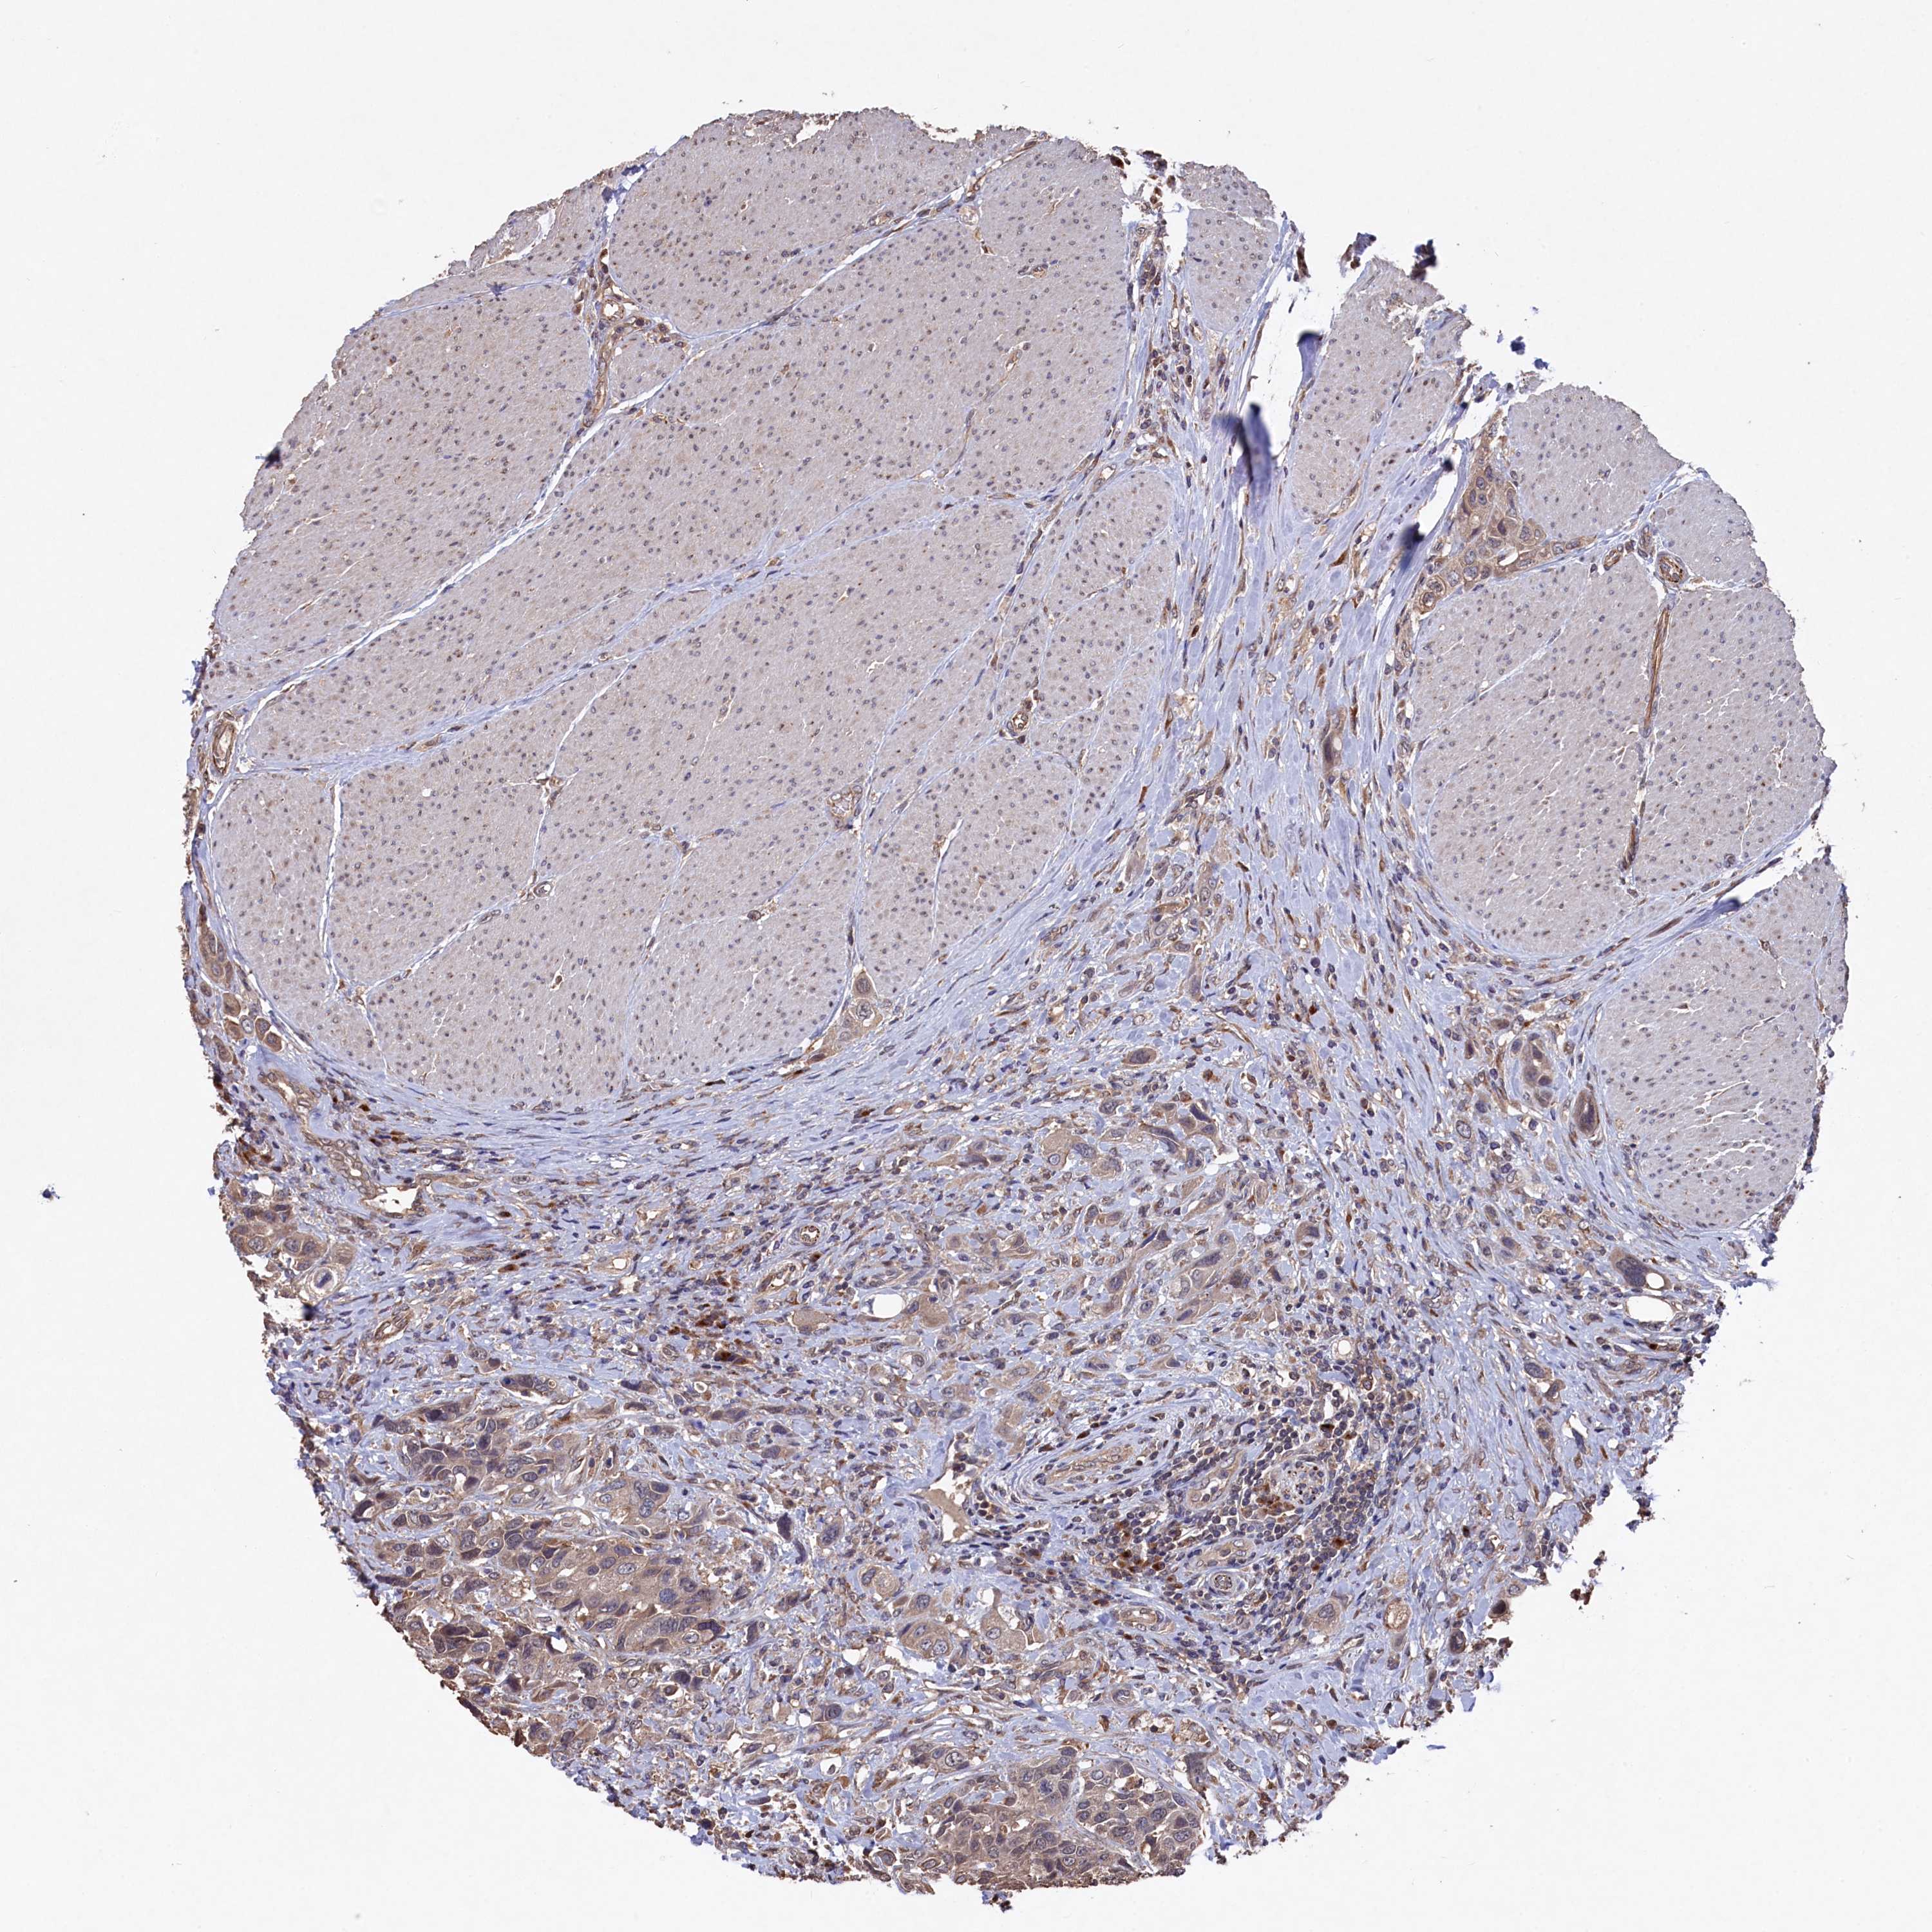

UROTHELIAL CANCER - Protein expressioni

A mouse-over function shows sample information and annotation data. Click on an image to view it in a full screen mode. Samples can be filtered based on level of antibody staining by selecting one or several of the following categories: high, medium, low and not detected. The assay and annotation is described here.

Note that samples used for immunohistochemistry by the Human Protein Atlas do not correspond to samples in the TCGA dataset.

Antibody stainingi

Antibody staining in the annotated cell types in the current human tissue is reported as not detected, low, medium, or high, based on conventional immunohistochemistry profiling in selected tissues. This score is based on the combination of the staining intensity and fraction of stained cells.

Each image is clickable and will lead to virtual microscopy that enables deeper exploration of all samples and also displays staining intensity scores, fraction scores and subcellular localization as well as patient and tissue information for each sample.

Antibody HPA040916

Staining

High

Medium

Low

Not detected

Intensity

Strong

Moderate

Weak

Negative

Quantity

>75%

75%-25%

<25%

None

Location

Nuclear

Cytoplasmic/membranous

Cytoplasmic/membranous,nuclear

Urothelial carcinoma, High grade

Urothelial carcinoma, Low grade